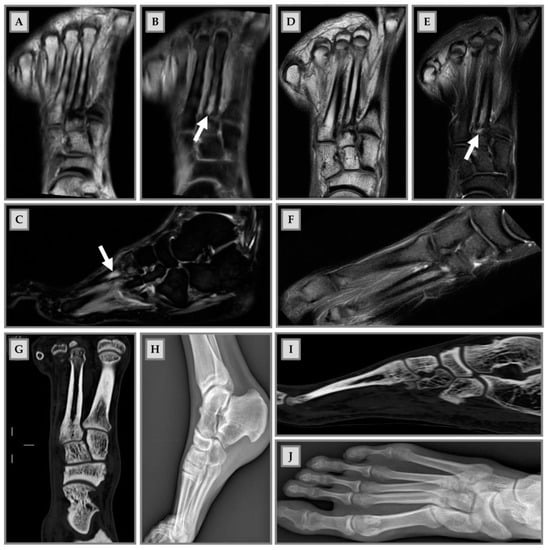

| [21] | 13 men and 3 women | Mean age: 22.9 ± 2.7 | Running | Pubic bones Hips Knee Ankle | Preseason and postseason | MRI | 14 of the 16 athletes had BME lesions before the start of the season: 31/45 were in the ankle joint and foot; 26/45 fluctuated during the season, with new lesions occurring (9/45) and old lesions disappearing (10/45), without causing any symptoms | The observed fluctuation pattern could indicate that BME participate in the normal bone remodeling process and, within 7 months, does not cause symptoms |